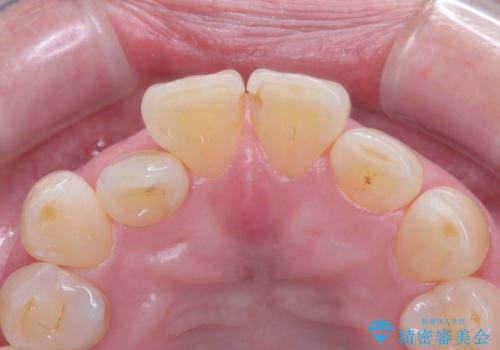

- 前歯の隙間とへこみが気になり、特に舌で触ると気になってストレスを感じるとのことで来院された患者様です。

上下ともに軽度の叢生があり、下顎がやや前突傾向にあったため、本来であれば矯正治療が第一選択となります。矯正によって下の前歯を後方に移動させることで、咬み合わせの改善とともに前歯のデコボコも整えることができます。

しかし、患者様はワイヤー矯正もマウスピース矯正も「絶対にしたくない」との強いご希望がありました。

上下に叢生(歯のデコボコ)と反対咬合があるため、本来であれば矯正治療が最も理想的な治療選択となります。

矯正によって歯並びや咬み合わせを整えた後、必要に応じて歯の形や色を整えるためにホワイトニングやセラミック治療を行うことで、より自然で美しい仕上がりが期待できます。